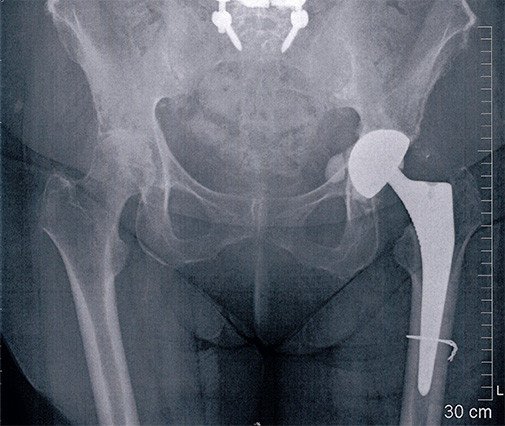

Bei der 73-jährigen Patientin wurde aufgrund einer Hüftarthrose vor 1 1/2 Jahren auf der linken Seite eine Hüfttotalprothese eingesetzt. Nach anfänglich gutem Verlauf, kam es zu einem Stolpersturz mit anschliessend persistierenden Schmerzen auf der Hüftaussenseite und schmerzhaftem Hinken.

Die weiteren Abklärungen zeigten, dass die Hüftmuskulatur teilweise abgerissen war. Die Hüfte wurde revidiert. Der Teilabriss des Hüftmuskels (Musculus glutaeus medius) konnte intraoperativ bestätigt werden. Deshalb wurde die Hüftprothese wieder ausgebaut. Der Ausbau eines zementfreien Schaftes macht zumeist die Längsspaltung des Oberschenkelknochens nötig. Der Muskel wird mit starken Fäden gefasst, die durch den Oberschenkelknochen gezogen werden. Die Nähte werden zusätzlich über eine Schraube gesichert. Meistens wird auch die Hüftpfanne entfernt. Zum einen kommt es sonst zu einem schmerzhaften Reiben zwischen dem Oberschenkelknochen und der Pfanne und zum andern wird die Pfanne meist sicherheitshalber entfernt, um eine evtl. vorhandene Infektion antibiotisch wirkungsvoll behandeln zu können (mit einem zurückgelassenen Implantat ist eine antibiotische Behandlung meistens schwierig).